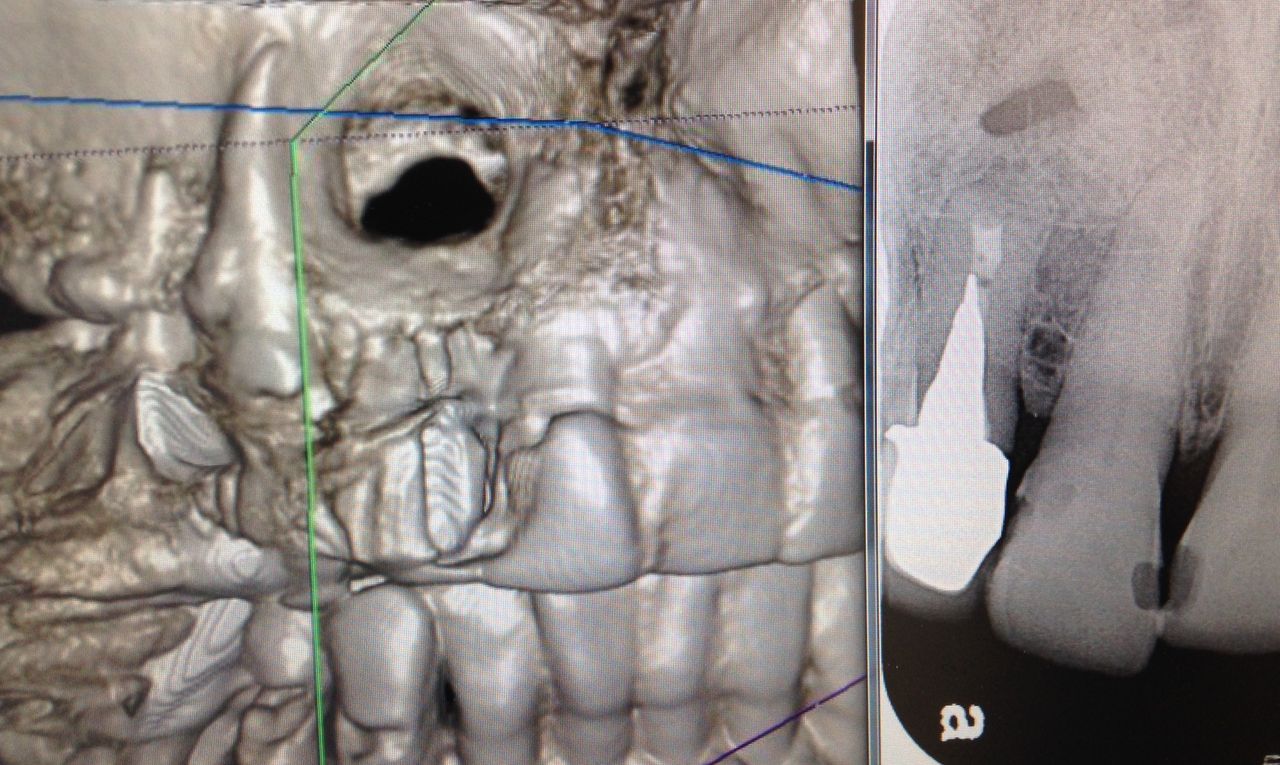

先日に書いたように完全に細菌を取り除くことはできません。

ので、外科的な治療が必要な歯もあるんです。

こんなに大きな穴でも、治ります。

少し根っ子を削るので、短くはなりますが。